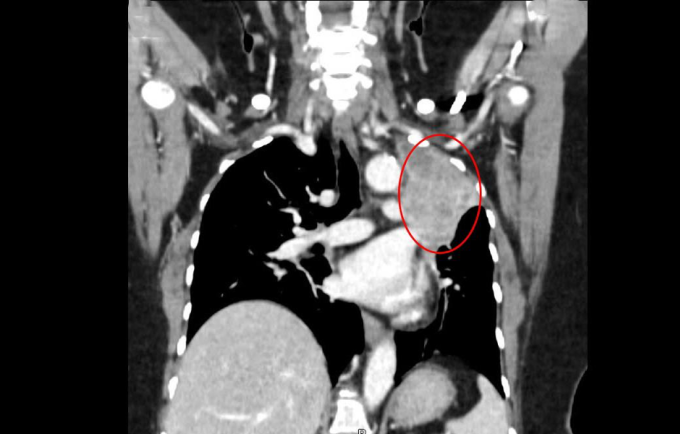

BS.CKII Nguyễn Trần Anh Thư, khoa Ung Bướu, Trung tâm Ung Bướu, cho biết các khối u ở não gây ra triệu chứng tương tự đột quỵ khiến người bệnh nhầm lẫn. Các khối u này có khả năng cao do ung thư di căn. Bác sĩ chỉ định chụp CT lồng ngực thùy trên phổi trái cho thấy khối tổn thương kích thước hơn 7 cm, bờ gồ ghề, gây xẹp phổi xung quanh.